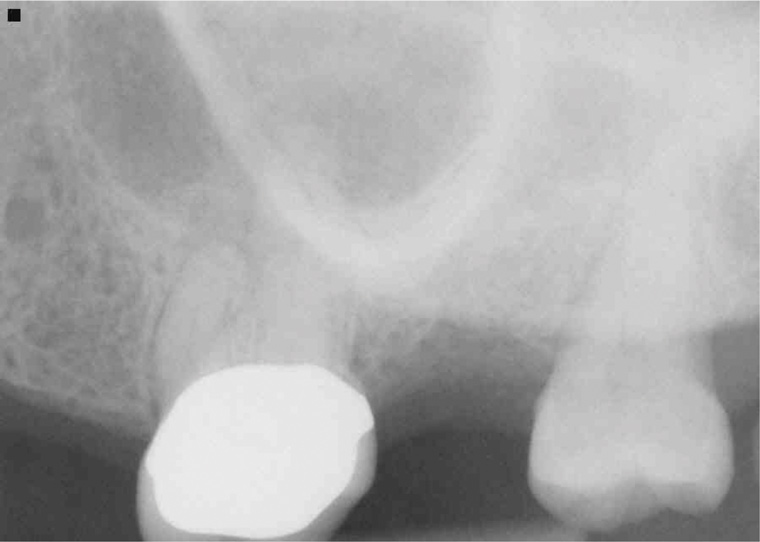

Because of its high resolution and ability to discern between bone and soft tissue, CBCT is the gold standard radiographic exam for the diagnosis of MSEO.2,12,18,20 CBCT imaging provides several advantages over traditional 2-dimensional dental radiographs. On periapical radiographs, anatomic noise imparted by the overlapping structures of the maxillary sinus and zygomatic process can conceal the inflammatory changes associated with apical periodontitis.9,29 Furthermore, 2-D radiographs do not adequately describe the anatomical relationship between the teeth and the sinus floor (Figure 2).3,9

(2.) Radiograph of PAO showing necrotic tooth with sinus pathosis obscured by the zygoma.

Figure 2